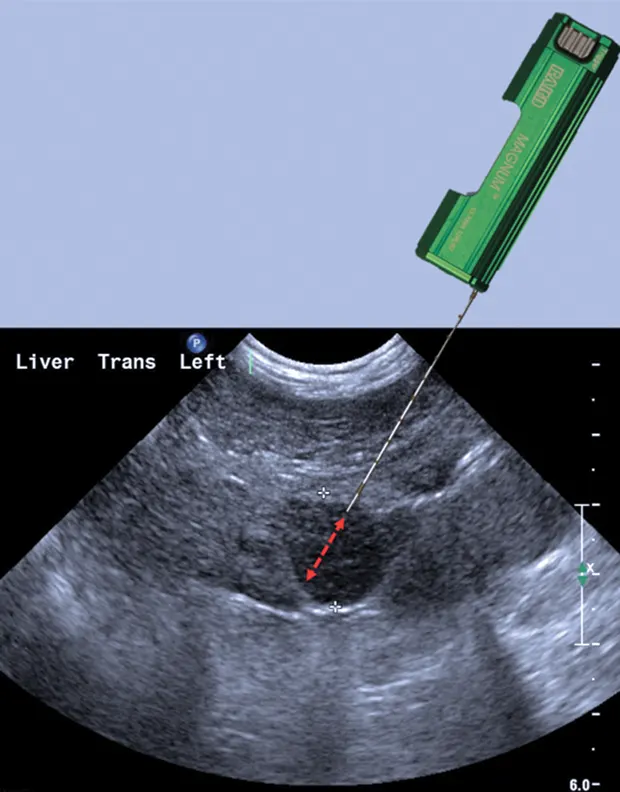

Larger-gauge biopsy devices (14-gauge) increase the risk for hemorrhage, especially with passage of the needle deep into the liver. However, a major limitation of needle biopsies is the size of the sample retrieved, so a balance between patient safety and sample size needs to be considered.4,5 Biopsy needles vary in actual length and in length of the biopsy stylet for the core liver tissue to be obtained (typically 12, 15, or 20 mm long). Semiautomated devices tend to have a fixed stylet length, whereas biopsy length can be altered with some of the fully automated devices. The fully automated biopsy device (Figure 3A; see Image Gallery) advances into the tissue a set distance depending on the length of the inner stylet that receives the tissue. This distance should be taken into account before firing the device to ensure that a proper specimen is likely to be collected and that non-target tissues are not sampled. For the semiautomated biopsy device, the inner (receiving) stylet is manually advanced prior to firing the outer cutting portion of the biopsy device (Figure 3B; see Image Gallery). On average, 3 to 4 quality samples are taken and placed in formalin for routine histopathology. Other types of sample handling will be required for determining copper content or specific types of tissue testing, as well as for culture and susceptibility testing. The clinician should be prepared ahead of time for the type of fixation or sample handling procedures so that the tissue sample is fresh and handled in an appropriate fashion.

Biopsy needle tract within the patient after firing and just before removing the biopsy device (B). Post-biopsy hemorrhage often collects between hepatic lobes as seen in this image (white arrow heads) (C). The echogenic fluid represents acute hemorrhage. Color flow Doppler post-biopsy ensures there is no persistent hemorrhage in the peritoneal space (D). Power Doppler imaging is the most sensitive form of Doppler to detect the presence or absence of blood flow.

Step 4: Plan the Trajectory

There are 4 key steps to ensure proper needle placement. First, the needle should always be oriented with the long axis of the transducer to ensure needle visualization throughout its length and through the entire process. Always know where the tip of the needle is. The second step is to realize the transducer's orientation to anticipate from which direction of the monitor the needle will enter. In general, enter from the same side of the transducer (transducer notch) for biopsies and fine-needle aspirates (5B). Anticipate exactly where the needle tip will enter the patient relative to the transducer to visualize the tip immediately on the screen. Third, the angle of trajectory should be calculated based on the depth of the lesion. Deeper lesions require a steeper angle, and superficial lesions require shallow angles. Once the angle is planned, place the needle approximately 1 cm away from the head of the transducer, oriented in planned trajectory. Do not go perpendicular to the skin if the transducer is placed perpendicular to the skin, as the parallel configuration is the worst possible reflector, and the biopsy device will not be seen in the image. Make a small skin incision with a No. 11 blade to facilitate needle placement.

Step 5: Advance Needle

Preload the biopsy device before advancing in the tissue. Advance the needle to the near field and pick up the needle device in the scan plan. Then, advance the biopsy needle tip to the area of interest or focal lesion. Next, move the transducer to find the needle tip (ie, do not move the needle to find the transducer) and reassess trajectory. With the trajectory planned and the needle 1 cm away from the transducer, the needle can be advanced for a semiautomated device before firing the outer cutting sleeve. Visualize the needle throughout the entire process to ensure proper sampling of the lesion selected and avoid inadvertent needle placement.